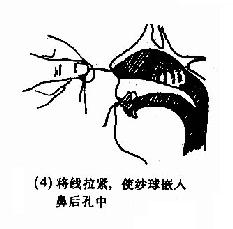

(2)后鼻孔填塞法(postnasal packing):先将凡士林纱条或消毒纱布卷迭成块形或圆锥形,长约3.5cm,直径约2.5cm,用粗线缝紧,两端各有约25cm长的双线,消毒备用。填塞时先收缩和表麻鼻腔粘膜,咽部亦喷有表面麻醉剂。用导尿管由前鼻孔沿鼻腔底部插入直达咽部,用镊子将导管从口腔拉出,导尿管尾端则留于前鼻孔外,再将填塞物上的双线系于导尿管,此时将填塞物由口腔送入鼻咽部,填塞于后鼻孔。为了减少患者痛苦,可用弯止血钳将填塞物在明视下送到悬壅垂的后上方,再将导尿管的鼻端向外拉紧。最后在前鼻孔处用一纱布球,将双线系于其上,以作固定,口腔端的线头可剪短留在口咽部,便于以后取出填塞物时作牵拉之用。后鼻孔填塞后,一般都需加行鼻腔填(图4-7)。鼻腔填塞物应于24~48小时内取出或更换,以防引起鼻窦及中耳感染等并发症。

图4-7 后鼻孔填塞法